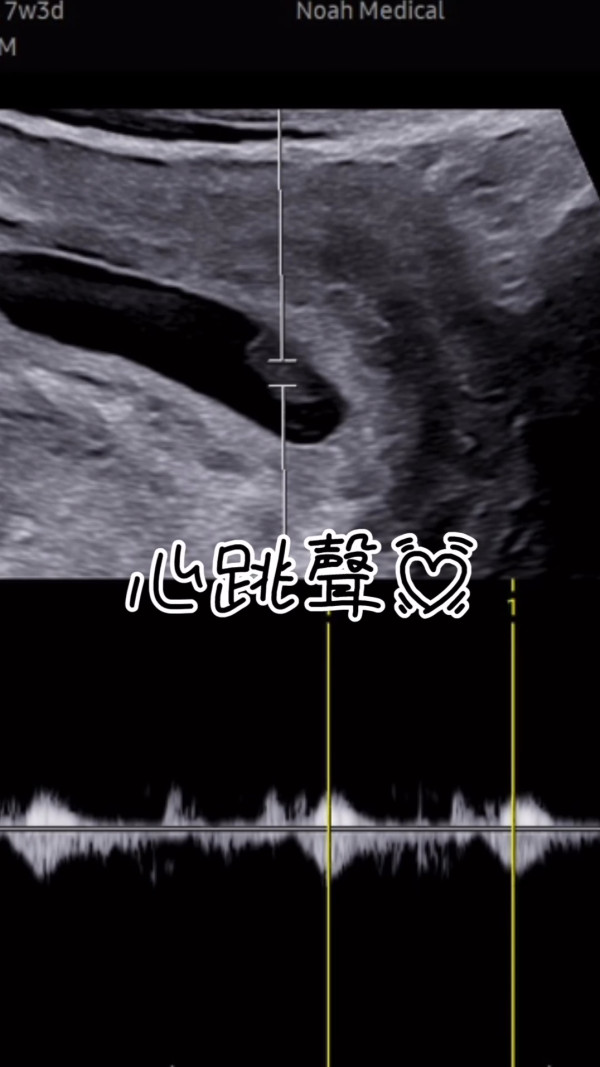

李清心只好耐心等待一星期後再檢查,不過等待的期間就令Katarina十分煎熬:「可惜(懷孕)周數太細喇,乜嘢都照唔到,聽唔到心跳,唯有休息一個禮拜等下次覆診睇吓有冇心跳啦。呢個禮拜真係好漫長,心情跌落谷底。」而她更晒出染有啡血及鮮血的衛生巾,表示持續有出血情況。

幸好經過充足的休息後,流血的情況終於停止,雖然目前BB的月份仍不大,不過她已經可以安心宣佈再度榮升人母好消息:「2026年,我又要做媽媽喇!」不少網民都在留言區祝福Katarina可以平安生產,紛紛慨嘆母親的偉大:「媽媽真係好偉大🥹」、「恭喜晒你呀❤️😍上天會保佑你的」、「一定會健康快樂😘」